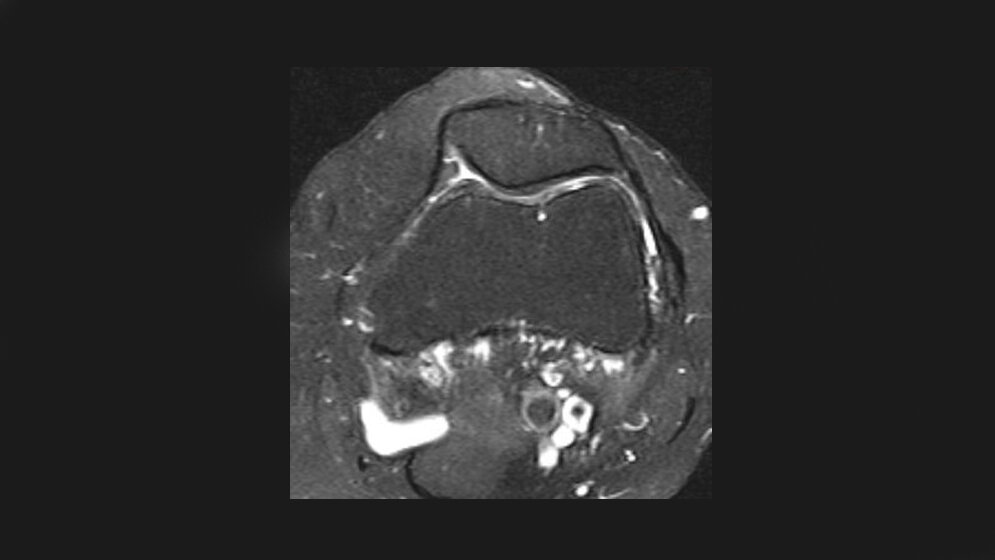

Die Patelladysplasie ist eine mögliche Anomalie des femoropatellaren Gelenks, die mit oder ohne Symptomatik vorkommen kann. Veränderungen des femoropatellaren Kongruenzwinkels korrelieren mit der patellaren Instabilität. Die Symptomatik, klinischen Merkmale und bildgebenden Verfahren haben eine große Breite an möglichen Ursachen und Möglichkeiten.

Dysplasia of the patella is one of the femoropatellar joint disease with or without symptoms. Changes of the femoropatellar congruence angle correlate with the presence of patellar instability. The symptoms, clinical features and imaging modalities have a large variety of causes and possibilities.